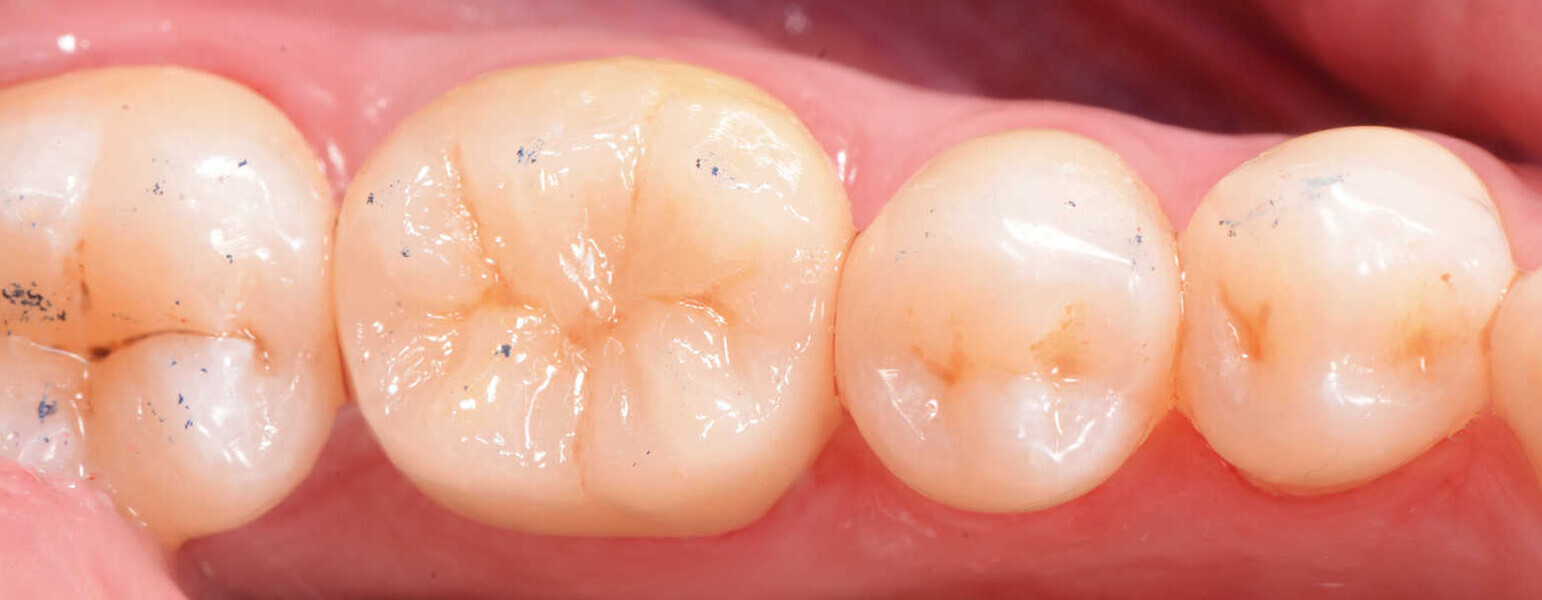

Figs. 12a y 12b. Vista final lateral y oclusal.